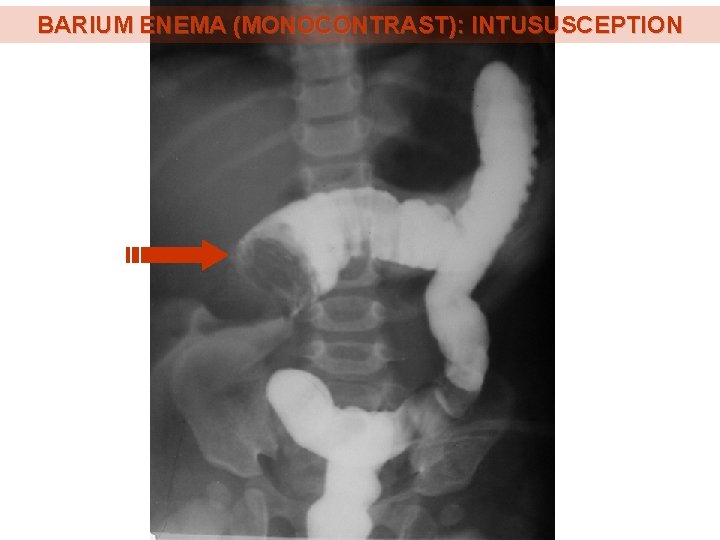

BARIUM ENEMA (MONOCONTRAST): INTUSUSCEPTION